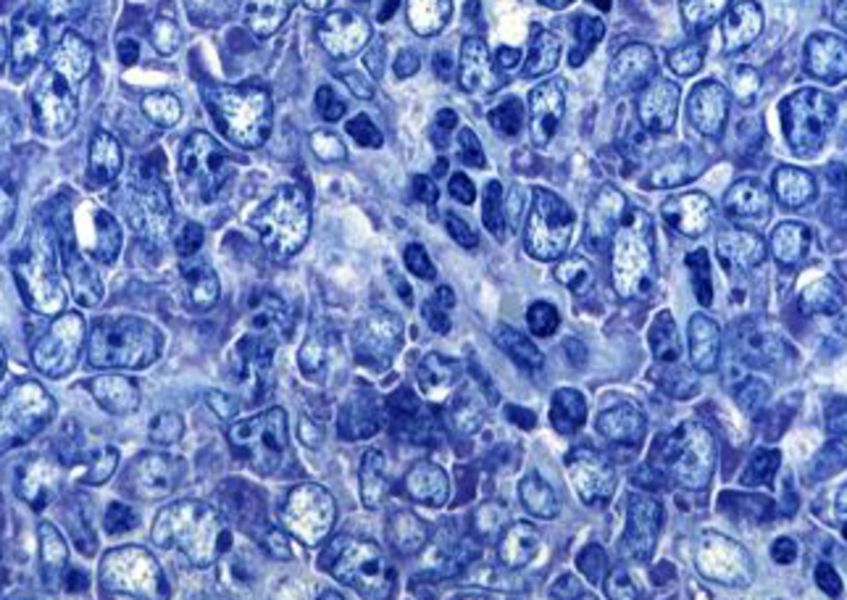

Diffuse großzellige B-Zell Lymphome

Ein Ziel unserer Arbeitsgruppe besteht darin, ein besseres Verständnis der molekularen Entstehungsmechanismen der DLBCL Subtypen zu erlangen. Um dies zu erreichen, untersuchen wir die funktionelle Bedeutung verschiedener neuer Onkogene und Tumorsuppressoren, die in unterschiedlichen genetischen Screens identifiziert wurden. Weiterhin führen wir verschiedene Screening Verfahren wie beispielsweise "small hairpin RNA (shRNA) library screens" durch, um neue für die Lymphomgenese essentielle Signalkaskaden zu identifizieren. Dadurch erscheint es möglich, ein umfassendes Verständnis der molekularen Pathogenese dieser Erkrankungen zu erlangen. Darüber hinaus ist es unsere Absicht, neue therapeutische Zielstrukturen zu identifizieren, die im Rahmen einer spezifischen Lymphom Therapie genutzt werden können, um die Prognose betroffener Patienten zu verbessern.

Ein besonderer Schwerpunkt unserer Arbeiten liegt dabei in der Translation unserer Forschungsergebnisse in die Klinik. Dazu führen wir zahlreiche klinische Studien durch, in denen innovative Therapiekonzepte untersucht werden. Klinisch decken wir das komplette Spektrum der malignen Lymphome und verwandter Erkrankungen ab. Wissenschaftlich beschäftigen wir uns schwerpunktmäßig mit den diffusen großzelligen B-Zell Lymphomen, den Mantelzelllymphomen, Burkitt Lymphomen und den aggressiven T-Zell Lymphomen.